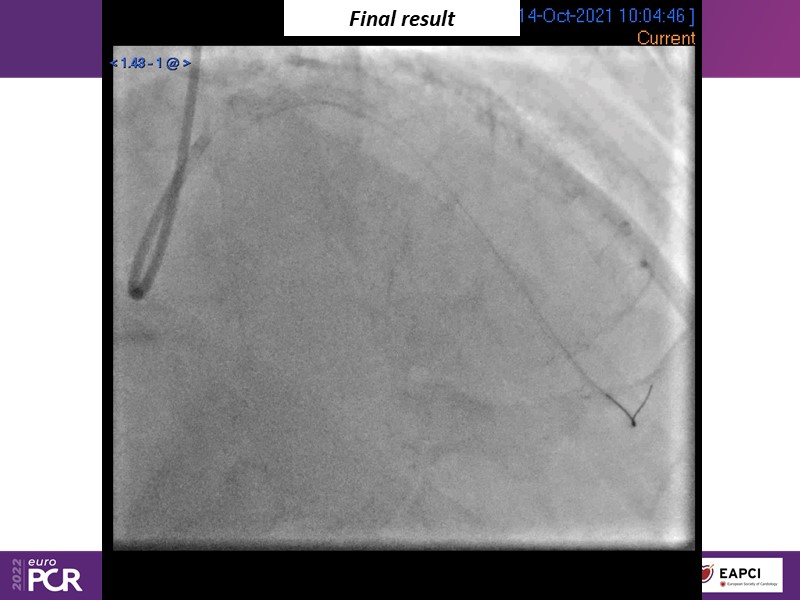

- To find out more about the application and mechanism of a sirolimus coated balloon for coronary artery disease treatment with case presentations in complex settings

- To understand how useful is a DES and DCB stent platform in complex coronary artery disease settings with case demonstrations and follow-up in diabetes mellitus